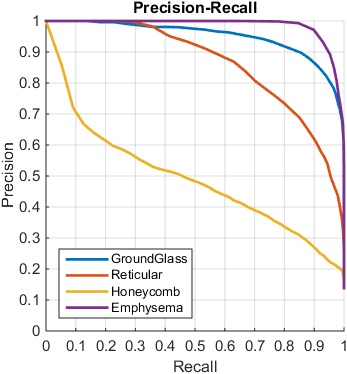

When constructing the FV-encoded features, , the local convolutional image descriptors are pooled into Gaussian components, producing a dimensionality as high as 16K [21]. We further reduce the FV features to dimensions using PCA. The performance is empirically found to be insensitive to the number of Gaussian kernels and the dimensions after PCA. We compare the ILD classification performance with FV encoding, on the features pooled from different CNN layers, using area-under-the-curve (AUC) values (in Table 5) and F-scores (in Table 6), respectively.

When evaluated using a smaller ILD dataset, the same as the one used in [11, 1] of 18k CT slices, FV order-less encoding is effective as demonstrated in Table 7. The unordered pooling operating on the first CNN convolutional layer conv1 produces the overall best quantitative results, especially for honeycomb. Despite residing in the first layer, the filters and activations on conv1 are still the integrated parts of a deep network since they are learned through back-propagation from deeper layers. From Table 7, FV encoding with deeply-learned conv1 filter activations produces the best ILD classification against FV encoding on other layers and without FV. Nevertheless, for the much larger dataset of 240k CT images under 5-fold CV, the computational complexity of FV encoding becomes the performance bottleneck. It could take an undesirably long time and huge memory requirement to calculate the FV Gaussian components and perform the feature encoding. In our experiments, we randomly select a smaller subset of deep activation features (1/3) to calculate FV encoding, which may limit the FV encoding performance. In this setting of sufficiently large amount of data, CNN models without FV encoding perform better.

| AUC | |||||||

|---|---|---|---|---|---|---|---|

| Disease | conv1 | conv2 | conv3 | conv4 | conv5 | fc6 | CNN |

| Ground Glass | 0.984 | 0.955 | 0.953 | 0.948 | 0.948 | 0.930 | 0.943 |

| Reticular | 0.976 | 0.958 | 0.954 | 0.951 | 0.950 | 0.939 | 0.917 |

| Honeycomb | 0.898 | 0.826 | 0.828 | 0.823 | 0.806 | 0.773 | 0.698 |

| Emphysema | 0.988 | 0.975 | 0.967 | 0.966 | 0.967 | 0.985 | 0.988 |